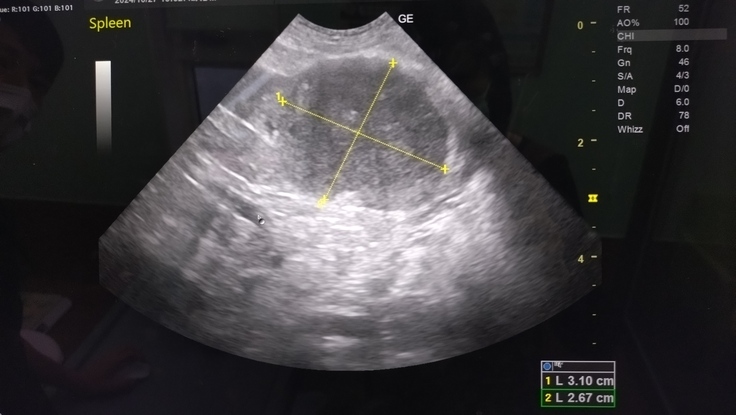

腎盂腎炎疑い一昨日の採血では腎臓肝臓の数値は問題ないので、可能性としては低いが、エコーで見ると拡張してくるので確認。エコー所見で腎盂腎炎はなし。

腹水がまた溜まってる。

エコーの白みはそこまで強くはないが、また腹膜炎が起きている可能性が高い。

腹膜炎と膀胱炎の炎症により発熱した可能性が高い。